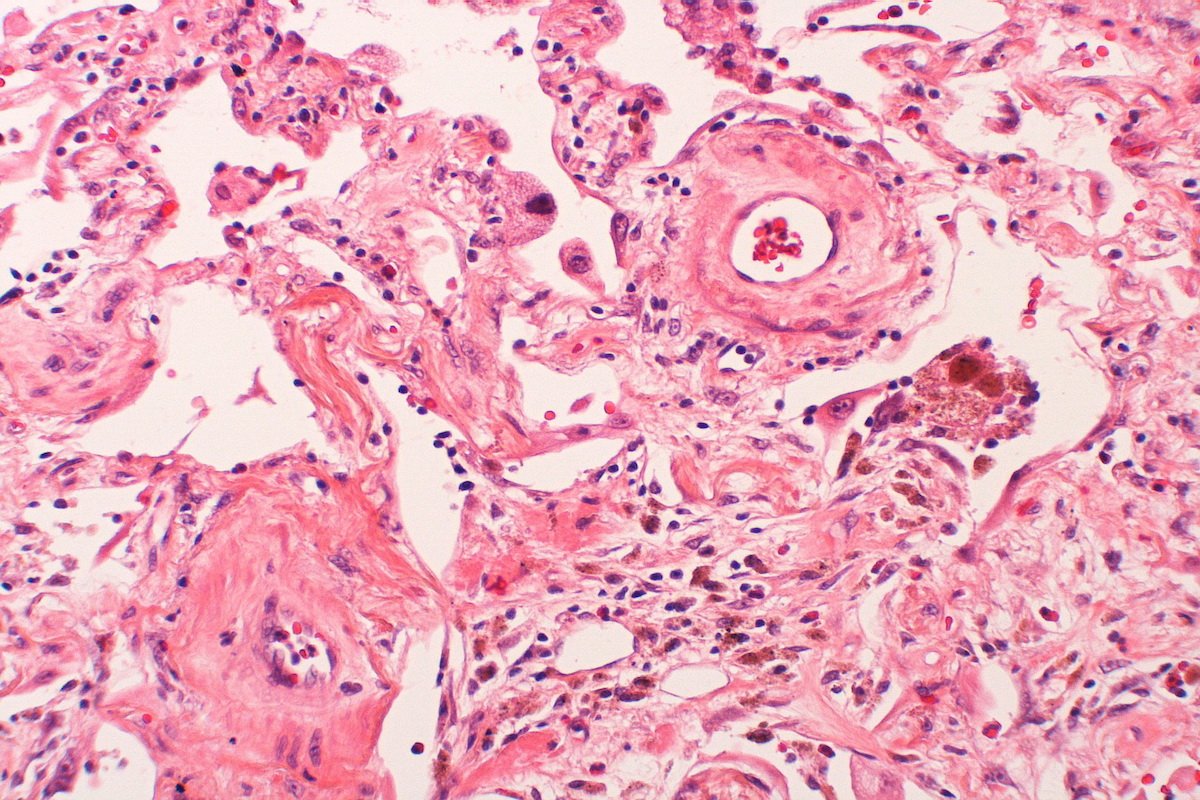

Naukowcy z nowojorskiego zespołu Rensselaer Polytechnic Institute we współpracy z kolegami z Yale University wydrukowali za pomocą drukarki 3D strukturę przypominającą skórę wyposażoną w ludzkie komórki śródbłonka i perycytów, co sprawia, że mogą się w niej rozwijać naczynia krwionośne. To krok milowy w badaniach klinicznych nad przeszczepami skóry.

Lekarze przeszczepiali już skóry wydrukowane za pomocą bioatramentu. Niestety do tej pory, z racji tego, że skóra nie była wyposażona w naczynia krwionośne, obumierała, a takie przeszczepy były traktowane jako rozwiązania tymczasowe. Dzięki innowacyjnemu osiągnięciu badaczy, teraz może się to zmienić.

Naukowcy twierdzą, że tkanka, nad którą pracują, może zrewolucjonizować metodę leczenia głębokich oparzeń. Jak podaje New Atlas, przeprowadzono już badania na myszach. Przeczepiono im na otwarte rany fragmenty wydrukowanej skóry. Efekty były zdumiewające - po czterech tygodniach naczynia krwionośne myszy połączyły się z wydrukowanymi.